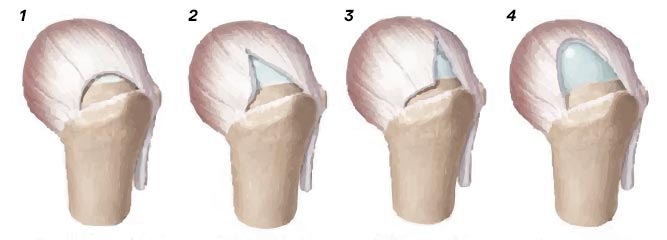

Erkrankungen und Verletzungen der Rotatorenmanschette: Ursachen, Ausprägungen und Behandlungsmöglichkeiten

Teilabriss der Rotatorenmanschette

1. Halbmondförmiger Abriss

2. V-förmiger Abriss

3. L-förmiger Abriss

4. U-förmiger Abriss